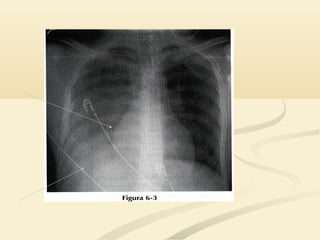

 El signo de la silueta puede ser engañoso en una placa pocoEl signo de la silueta puede ser engañoso en una placa poco

penetrada.penetrada.

 Si no puedes ver la columna a través del corazón, la placa tieneSi no puedes ver la columna a través del corazón, la placa tiene

una penetración insuficiente y el signo de la silueta puede induciruna penetración insuficiente y el signo de la silueta puede inducir

a error.a error.

 El borde cardíaco derecho se superpone a la columna y no haceEl borde cardíaco derecho se superpone a la columna y no hace

prominencia en el pulmón derecho; la densidad de hueso de laprominencia en el pulmón derecho; la densidad de hueso de la

columna oculta la interfase pulmón/corazóncolumna oculta la interfase pulmón/corazón

OJO!!!!!OJO!!!!!  El signode la silueta puede ser engañoso en una placa pocoEl signo de la silueta puede ser engañoso en una placa poco penetrada.penetrada.  Si no puedes ver la columna a través del corazón, la placa tieneSi no puedes ver la columna a través del corazón, la placa tiene una penetración insuficiente y el signo de la silueta puede induciruna penetración insuficiente y el signo de la silueta puede inducir a error.a error.  El borde cardíaco derecho se superpone a la columna y no haceEl borde cardíaco derecho se superpone a la columna y no hace prominencia en el pulmón derecho; la densidad de hueso de laprominencia en el pulmón derecho; la densidad de hueso de la columna oculta la interfase pulmón/corazóncolumna oculta la interfase pulmón/corazón